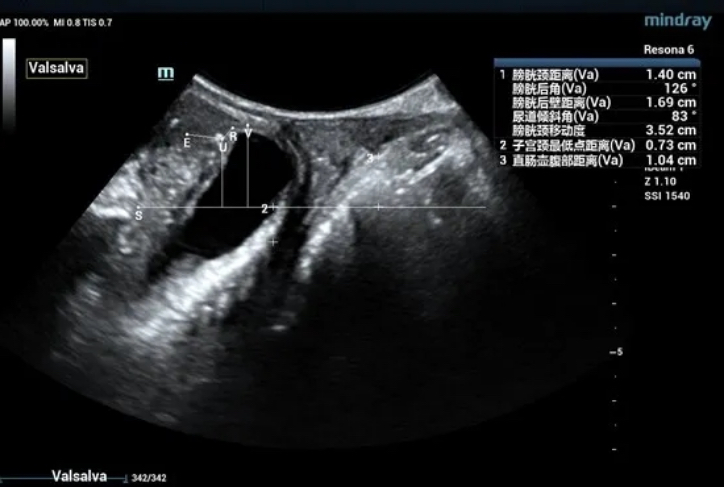

The bladder neck is located 21.2mm above the pubic symphysis at rest, the uterus is located 27.0mm above, and the rectum is located 10.8mm above (see Figure 1).

During maximal Valsalva maneuver, the bladder neck is 14mm below the pubic symphysis , the lowest point of bladder is 16.9mm below, the uterus is 7.3mm above and the rectum is 10.4mm below. The levator ani hiatus is 26.06cm2 (see Figure 2).

Figure 1 Two-dimensional ultrasonic measurement of pelvic floor structural parameters at rest

Figure 2 Two-dimensional ultrasonic measurement of pelvic floor structural parameters in Valsalva state

Obvious cystocele, increased mobility of bladder neck, increased urethral rotation angle, increased area of levator ani hiatus (see Figure 6 and Figure 7).